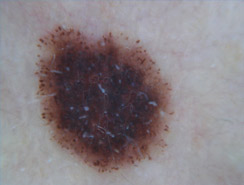

Lo studio e la diagnosi delle neoformazioni cutanee attraverso strumenti specifici indicati per un'analisi delle caratteristiche strutturali superficiali e profonde delle varie neoformazioni cutanee: dermatoscopia, dermalite a luci fotocromatiche, mappatura nevica con videodermatoscopia digitale.

Al fine di una corretta diagnosi dei nevi, e dunque di un'efficace prevenzione da forme tumorali, è indispensabile visionare in profondità i caratteri di ogni formazione nevica. Ciò è reso possibile dall'utilizzo del dermatoscopio e dalla concomitante mappatura nevica, con l' eventuale rimozione chirurgica o laser di: